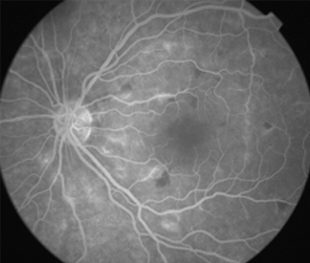

Angiografía OD

- Angiografía: teñido arterial, escape capilar, más tardíamente, no perfusion arteriolar y venular con teñido de las paredes vasculares y dilatación venosa.